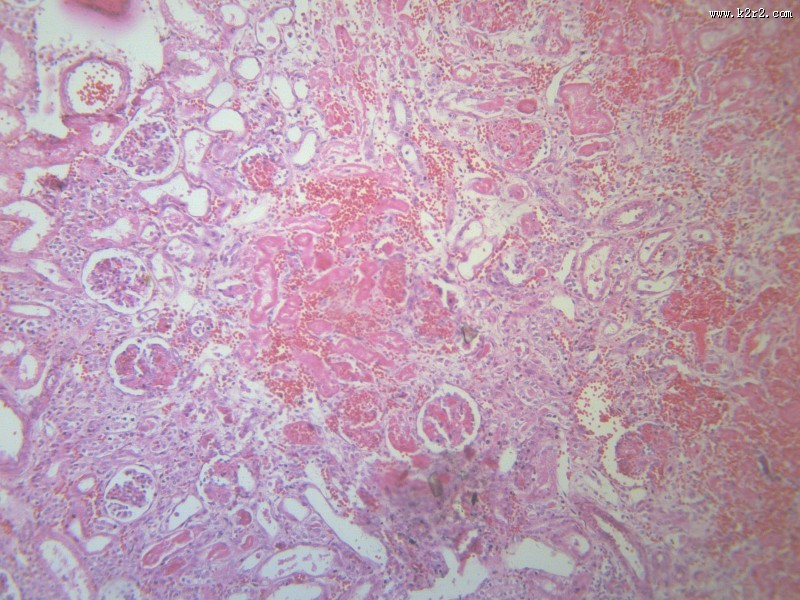

肾小管坏死 - 第9张

第 9 / 12 张

肾小管坏死

图集中 / 共有 12 张图片

肾凝固性坏死

肾小管水肿

医学

显微切片